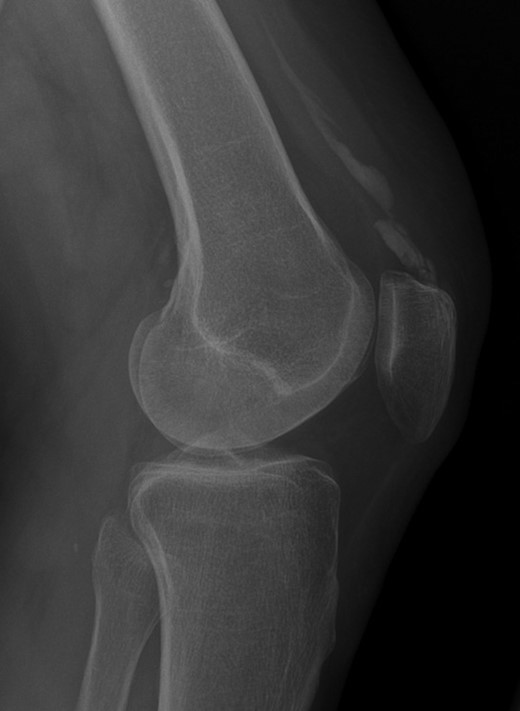

Radiographic appearance and MRI signal change confirmed calcification rather than ossification or enthesopathy. An unusual diagnosis of dystrophic calcification of the left quadriceps tendon was made (Figs 1–4).

Weight-bearing lateral radiograph of the patient’s knee shows extensive mineralization of the quadriceps tendon.